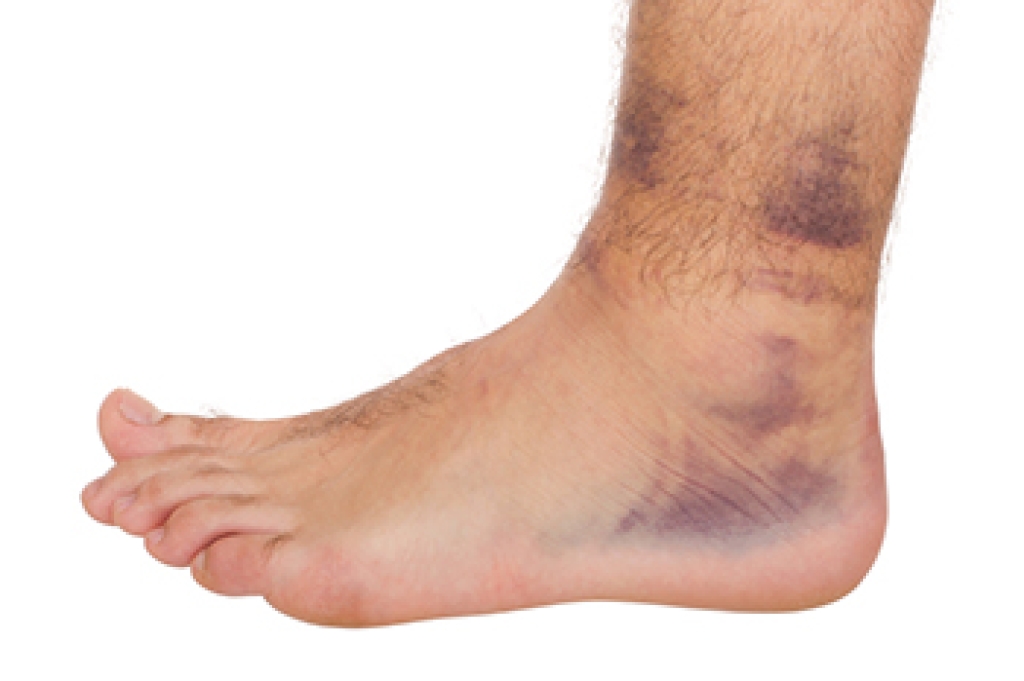

- Involves pressure or an injury, direct pressure on the tibial nerve for an extended period of time, sometimes caused by other body structures close by or near the knee.

- Different sensations, an afflicted person may experience pain, tingling, burning or other unusual sensations in the foot of the affected leg.

- The foot muscles, toes and ankle become weaker, and curling your toes or flexing your foot can become difficult.